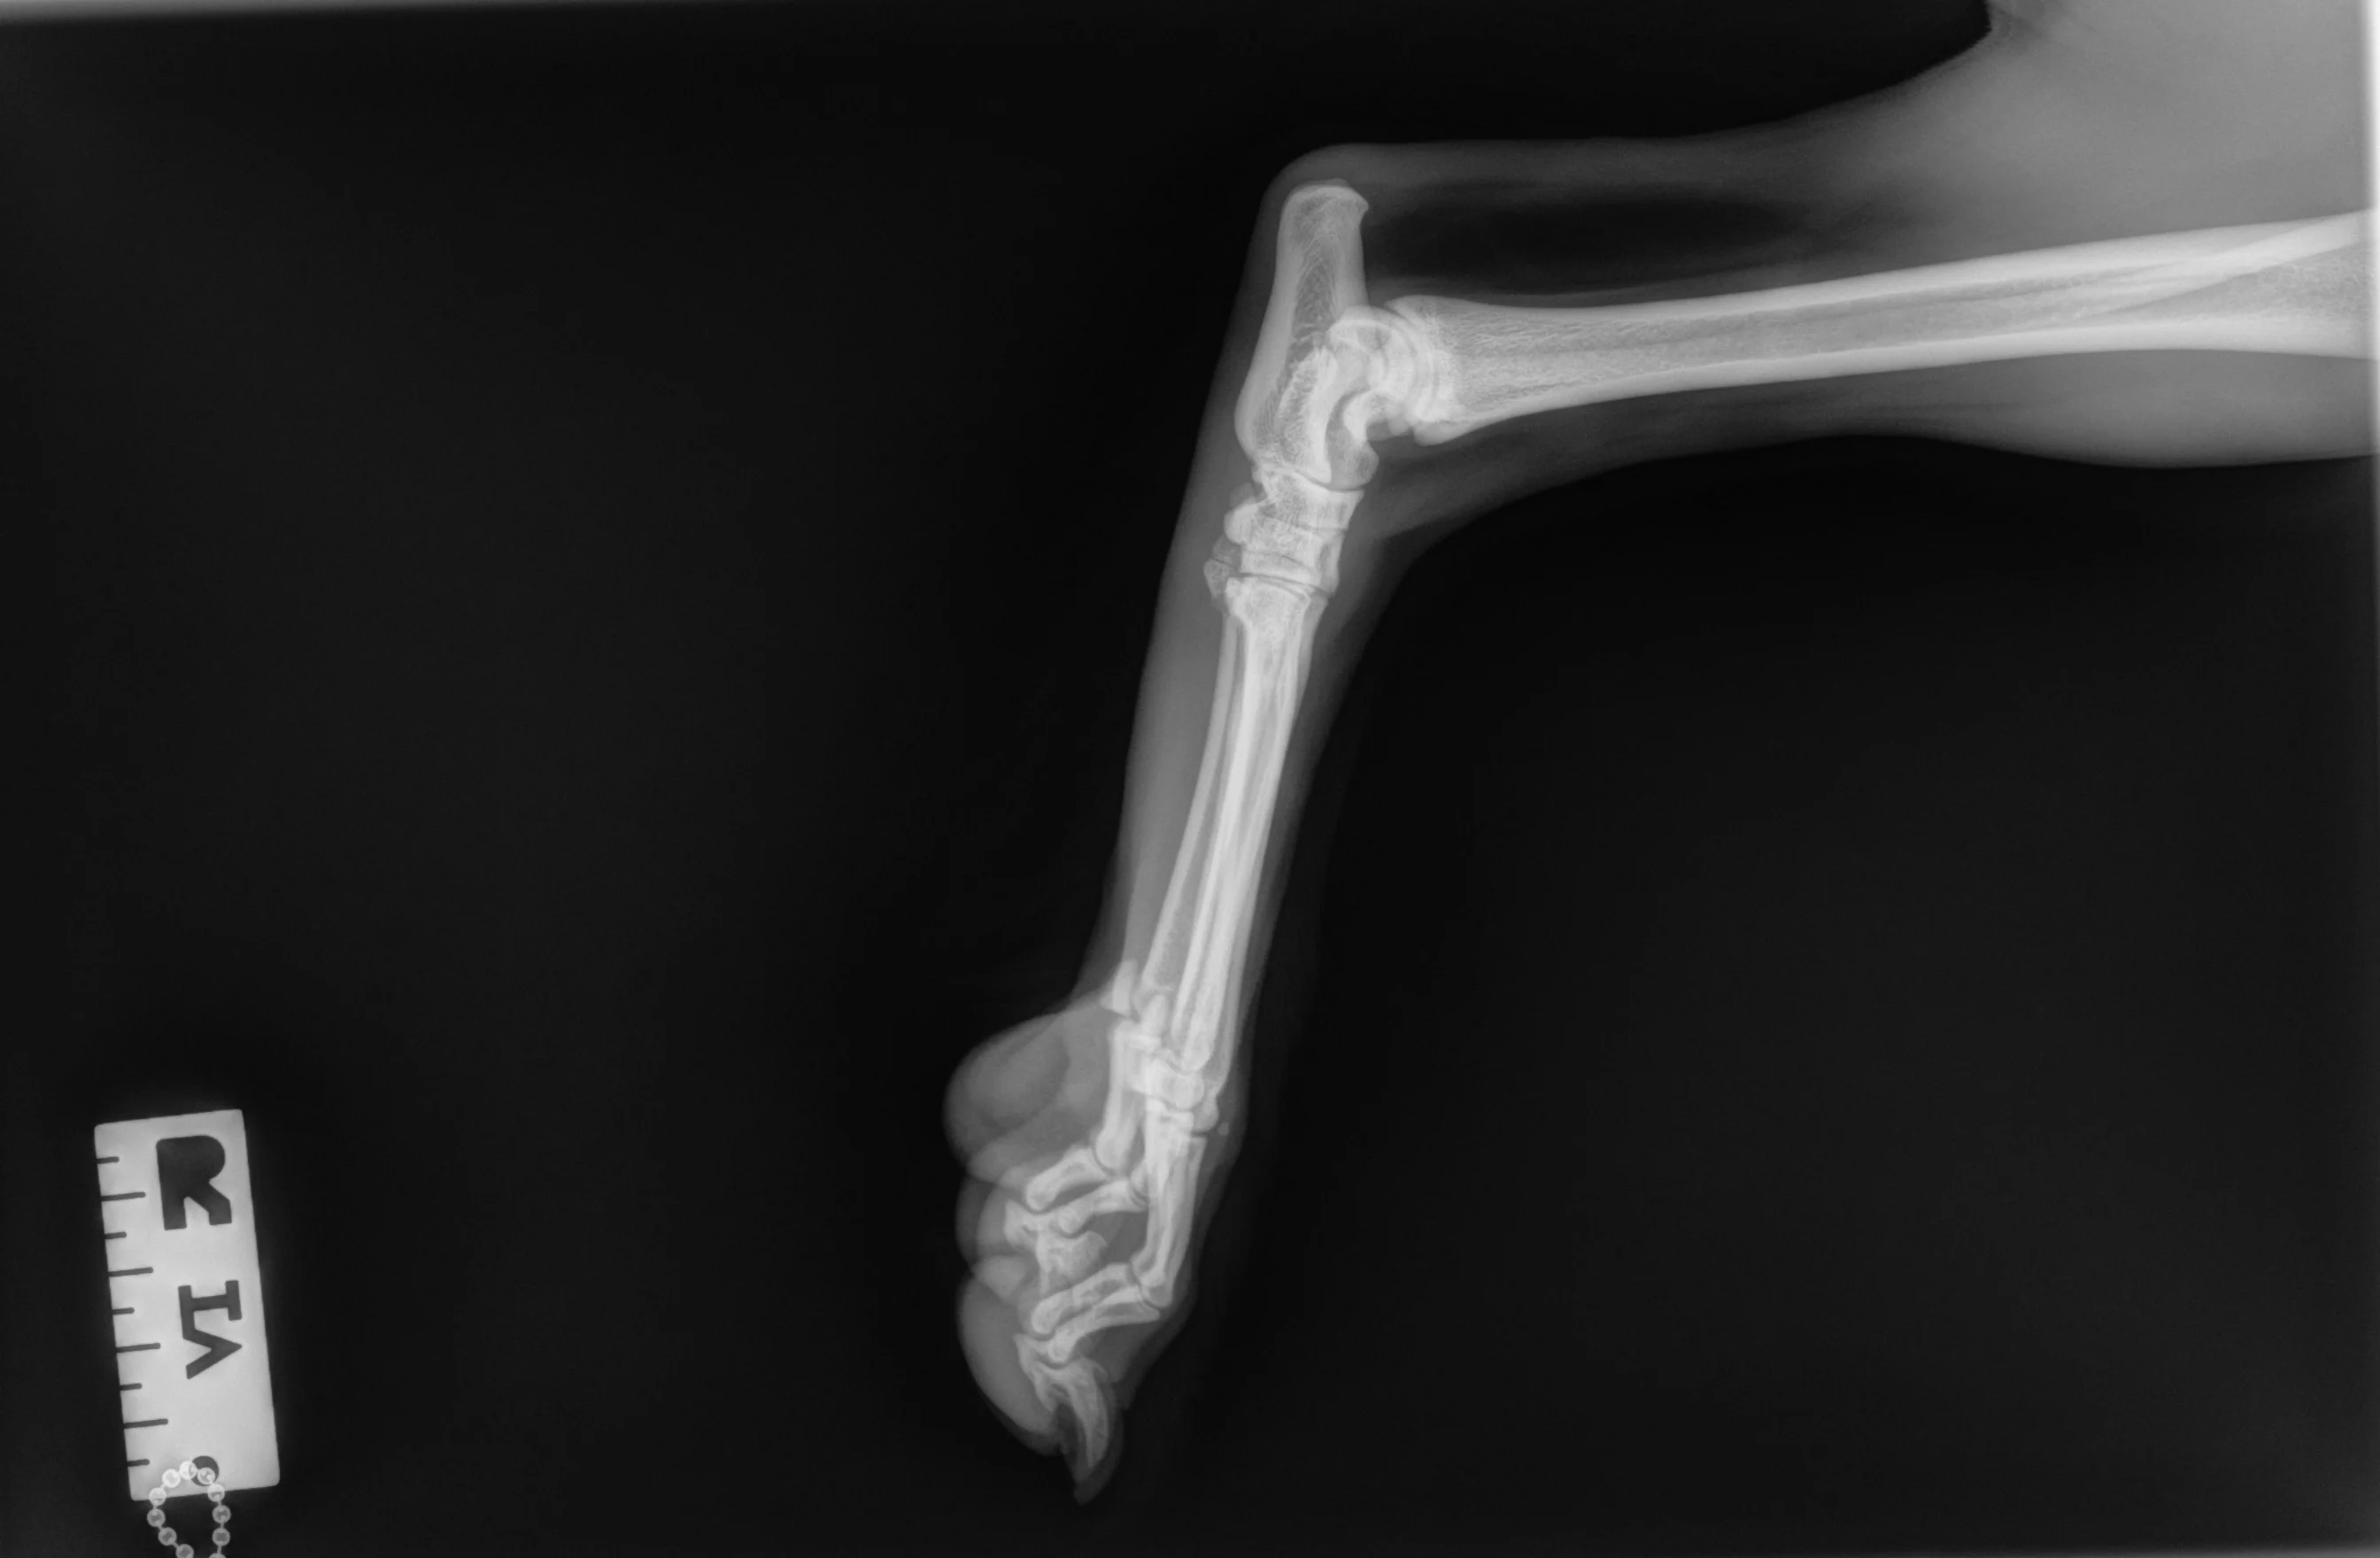

Author Insight

The trochlear ridges of the talus should be superimposed (gray arrow), and the calcaneus (dashed arrow) should not be foreshortened. The proximal (A) and distal (B) row of tarsal bones should align with clear superimposition, with visible joint space between the 2 rows of bones (white arrow). Perfect superimposition of the metatarsal bones (bracket) cannot occur because of the procurvatum of the foot. The dewclaw (if present) will lie caudally.